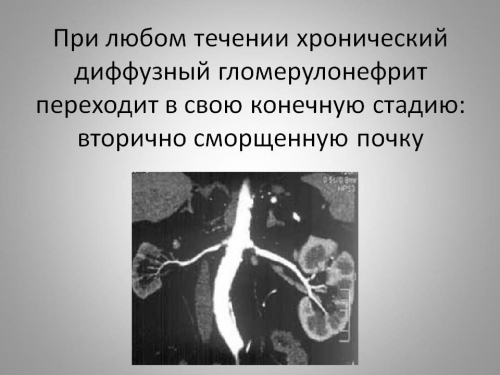

Механизм остро го диффузного гломерулонефрита